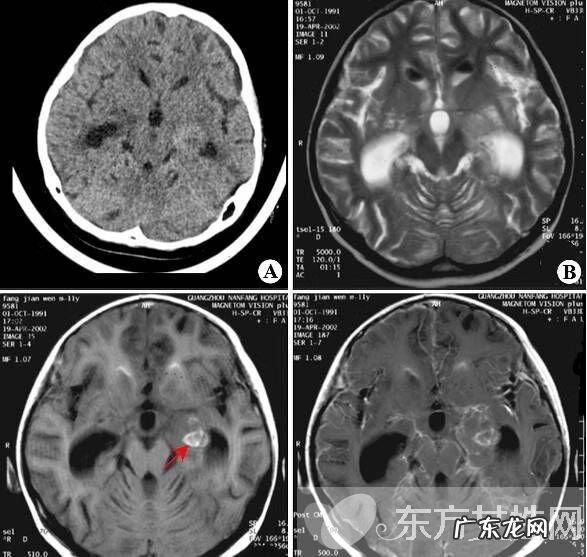

脑膜炎早期症状有哪些?脑膜炎分为病毒性脑膜炎、细菌性脑膜炎和结核性脑膜炎,以前两种居多,脑膜炎的严重程度主要取决于感染的神经系统部位,症状有轻有重 。